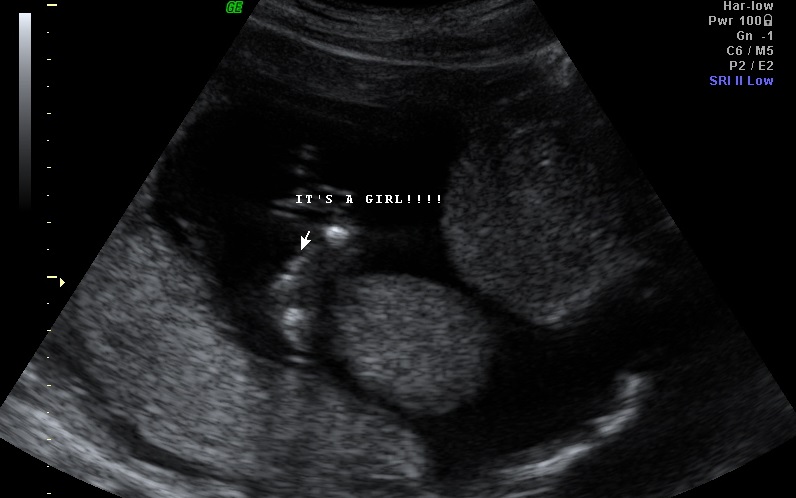

hello everyone :) this was taken at 14wks 6days at our 2d/3d gender scan U/S we already have a 19 month boy and i just want a 2nd opinion from another U/S tech please help thank youAttachment 12397Attachment 12398

Looks girly :)

Looks like my girls!